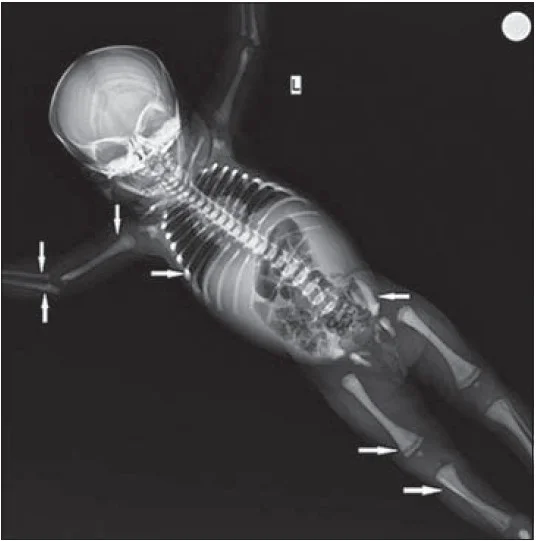

Examination of the Skeleton

- It’s better to have an X-ray photograph for each baby coming to necropsy.

Skull bones show loss of alignment, and they override each other due to shrinkage of the brain after death, known as Spalding’s sign. The brain becomes pulpy and grayish-red in color.